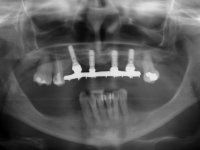

Após análise clínica e imagiológica foi proposto á paciente reabilitar o maxilar superior fazendo a colocação de 4 implantes e posteriormente ser reabilitada com uma Prótese Hibrida.Com a reabilitação proposta, também seria tentada a correção prostodontica da falta de apoio do lábio superior, desde que aprovada esteticamente pela paciente após um “Mock-up” prévio.

Inicialmente foram confecionadas duas novas próteses removíveis. O dente 1.3 foi extraído quando da colocação das próteses. Feito o estudo imagiológico necessário, foram colocados 4 implantes no maxilar superior. Após 3 meses de osteointegração foi feita a impressão para a confeção de ceras de articulação montadas em placa base aparafusadas aos implantes. Estas ceras foram utilizadas na recolha das relações inter-maxilares e na tentativa de proporcionar apoio ao lábio superior. Foi feita a prova de dentes com estes montados em placas base aparafusadas permitindo uma avaliação estética dinâmica muito interessante. Sendo validada esteticamente pela paciente, esta prova deu origem a uma muralha de silicone que orientou laboratorialmente a confeção da infraestrutura metálica. A infraestrutura metálica com os dentes montados em cera foi provada em boca, permitindo simultaneamente verificar a sua adaptação bem como a estética final. O trabalho final foi colocado em boca sendo acompanhado de instruções rigorosas de técnicas de higiene oral bem como da informação da necessidade de consultas de controlo periódicas.